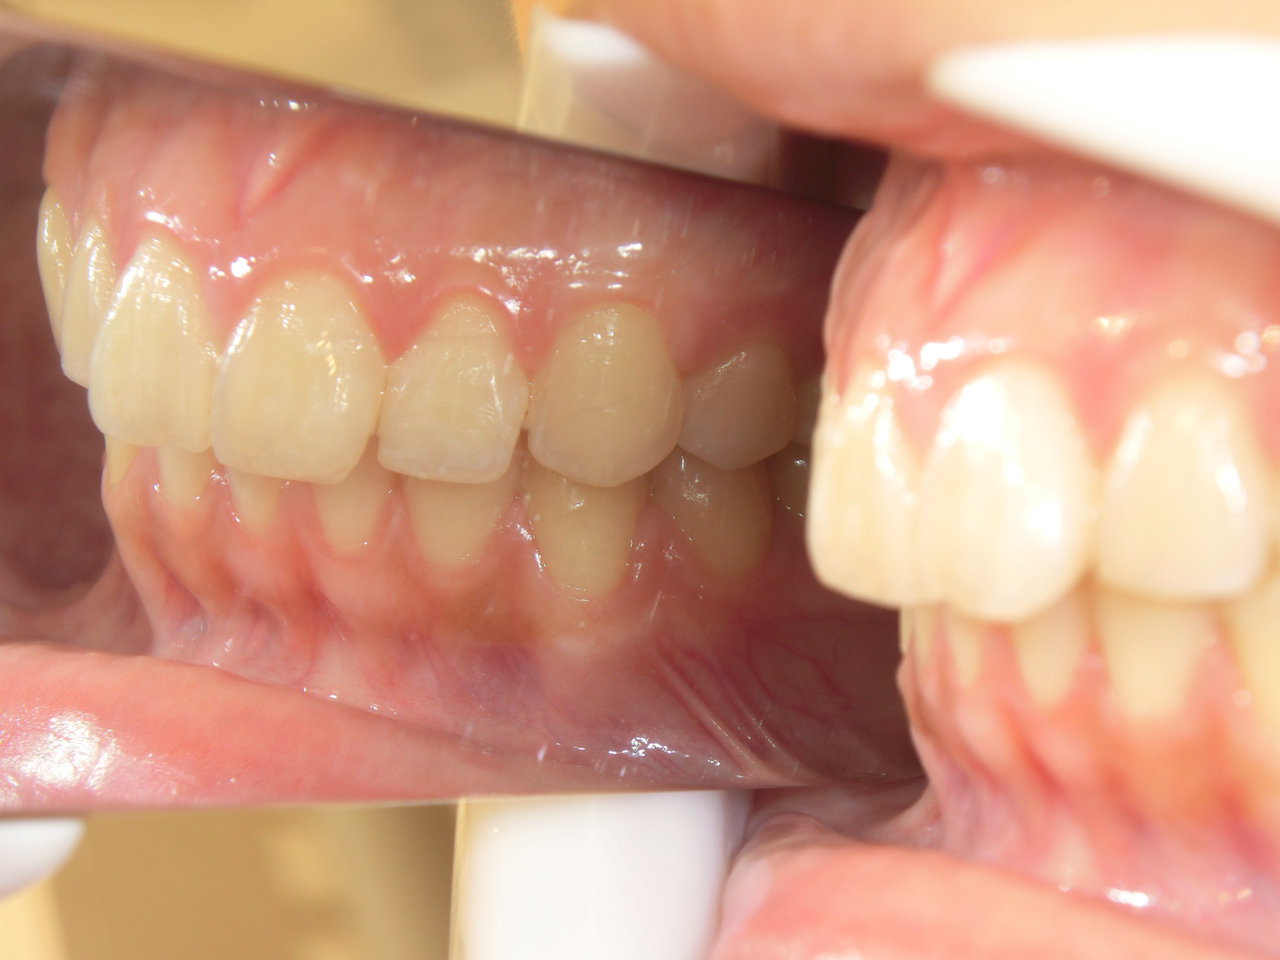

治療前

治療説明 歯科矯正でも目立ちにくい矯正方法であるマウスピース矯正で治療しました

治療期間 2年6か月

治療費用49,8000 円

治療後

治療の副作用(リスク)歯の動き方には個人差があり、予想された治療期間が延長する可能性があります。。マウスピースの使用状況、矯正歯科治療には患者さんの協力が必要であり、それらが治療結果や治療期間に影響します